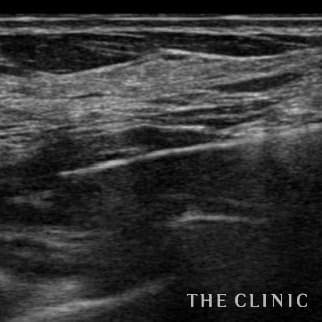

乳腺専用エコーを導入

術前後にエコー検査を行い、手術計画や結果についてを専門的に判断します。